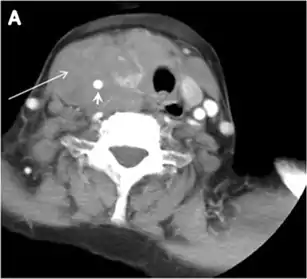

Fig. 4. A 45-year-old male patient presented with anterior mediastinal metastatic PTC lesions and occult primary on imaging. Histopathology examination of the resected thyroid gland revealed micro-foci of PTC; the largest, in the isthmus, measured 4 mm. a transverse greyscale ultrasound of the thyroid demonstrates homogeneous gland with normal echogenicity and size. No focal lesion or micro-calcifications. b Non-enhanced CT scan obtained as part of PET/CT examination shows a heterogeneous, large, relatively dense anterior mediastinal mass (white arrow) with peripheral calcification (arrowheads). Thyroid gland has normal CT appearance with no abnormal FDG uptake (not shown).[1]